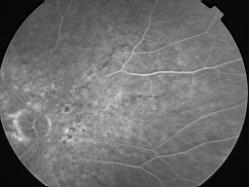

ASSOCIATION STRIES ANGIOIDES ET DYSROPHIE MACULAIRE RETICULEE

NEOVASCULARISATION